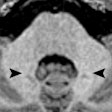

MRI spots HIV in the brain

March 13, 2017